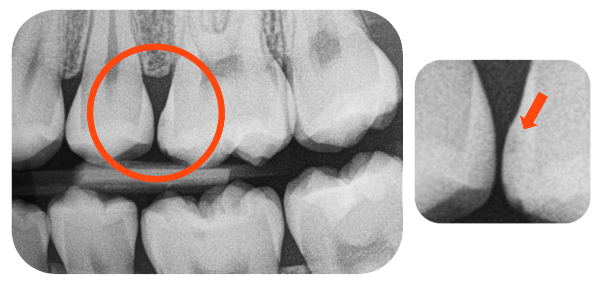

After Curodont Application